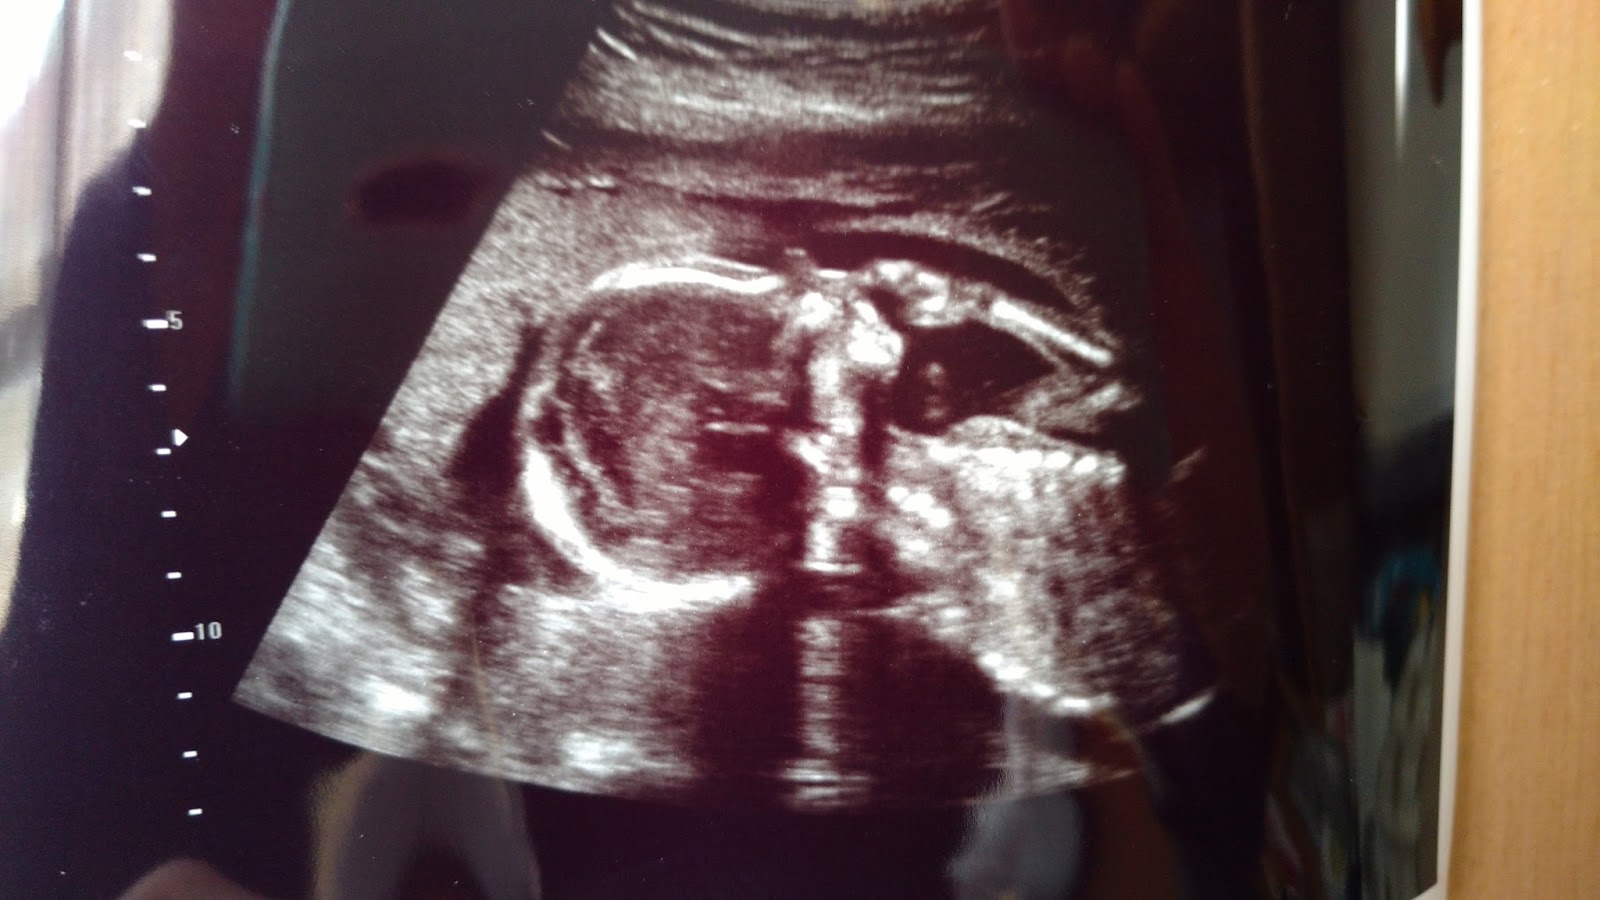

Ultrasounds from February 2014

Fetal Echocardiogram May 2014

When I was about 18-20 weeks pregnant, we went into have our anatomy ultrasound done with Kassia, and at that time we found out that something wasn't right with the development of her heart. We had to go back couple months later for a fetal echocardiogram to determine the severity of the defect and what her delivery might look like. On May 27, 2014 we were told that she has an Atrioventricular Septal Defect (avds or Ostium Primum). Her specific heart defect doesn't effect the ventricle much but it does effect her her left ventricle valve. She also has a small hole higher up between the atrial chambers.